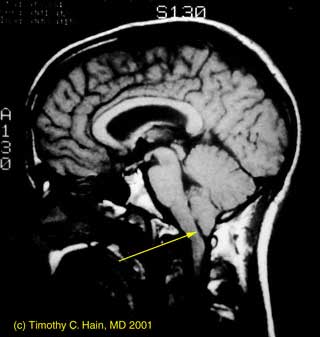

Pergeseran tonsil serebelum kebawah melewati foramen magnum. Biasanya batang otak masih tetap dalam posisi yang normal yang pada sebagian besar pasien dan kerap disertai dengan adanya SIRINGO(HIDRO)MIELIA

Diagnosis dapat ditegakan dengan mudah oleh pemeriksaan sken resonansi magnet (MRI). Pilihan tindakan terapi baginya adalah pemantauan klinis lanjutan dan intervensi bedah. Kasus yang mengalami progresivitas gejala atau gangguan klinis yang bermakna, baru merupakan indikasi untuk operasi. Tindakan operasi yang dilakukan biasanya adalah Kraniektomi fosa posterior, dan laminektomi servikal untuk dekompresi.